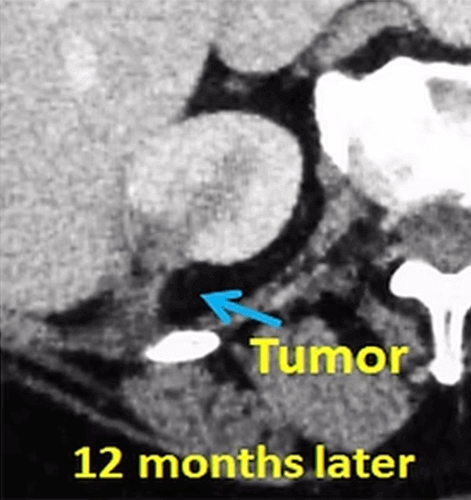

A 62-year-old female patient with cancer in her right kidney (red arrow) undergoes cryoablation with 3 needles. The control CT scans taken at 6 and 12 months after the procedure show progressive shrinkage of the tumor (blue arrow). There was no recurrence during the 4 years follow up.